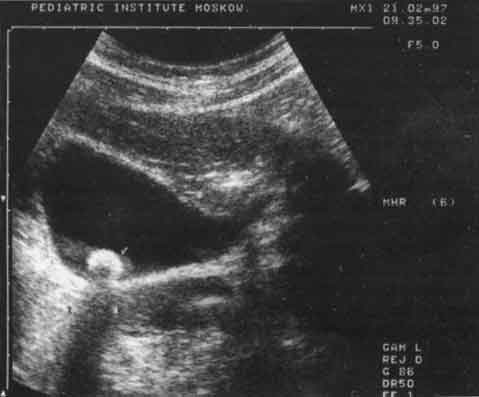

Изменения желчного пузыря были представлены в основном нарушением его формы - перегибы в области дна, тела (21%), S-образные перегибы (9%) и наличие перегородок и перетяжек (7%). У 12% детей имело место увеличение желчного пузыря, у 8% - утолщение стенок более чем на 2 мм, что является ультразвуковым признаком холецистита. У 0,5% детей в просвете пузыря были выявлены конкременты, размер которых не превышал 6 мм, из них у 82% они не были кальцинированы. Этот вывод был сделан на основании отсутствия "дистальной тени" за эхосигналом от конкремента. Оценка сократительной функции желчного пузыря позволила в 83% случаев выявить ее нарушение, причем в 71% из них оно носило гипомоторный характер. В ряде случаев перечисленные отклонения в состоянии желчного пузыря были смешанными. Чаще всего наблюдалось сочетание аномалий с увеличением желчного пузыря (рис. 3 - 5).

Рис. 3. Эхограмма желчного пузыря с S-перегибом.

Рис. 4. Эхограмма желчного пузыря при хроническом холецистите.

Рис. 5. Эхограмма желчного пузыря с конкрементом (обозначен стрелкой).